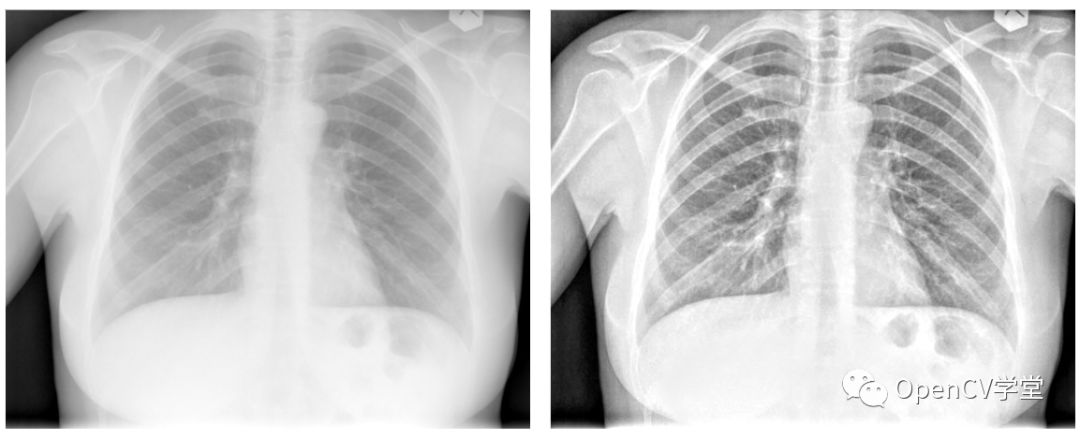

对于医学图像,该算法也能很好的起到增强作用:

原始的浑浊图像经过处理后变得非常清晰。

医学图像通常有很多都是16位的,该算法对16位依然有效,只是处理过程要稍作修改即可。